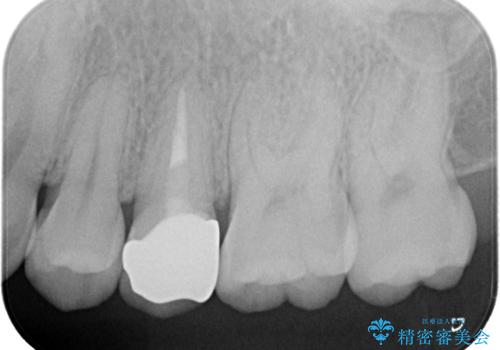

根管治療〜オールセラミッククラウン

根管治療を行なったのち、オールセラミッククラウンにて修復治療を行なっております。

根管治療を行なった歯は速やかに歯冠修復が必要です。